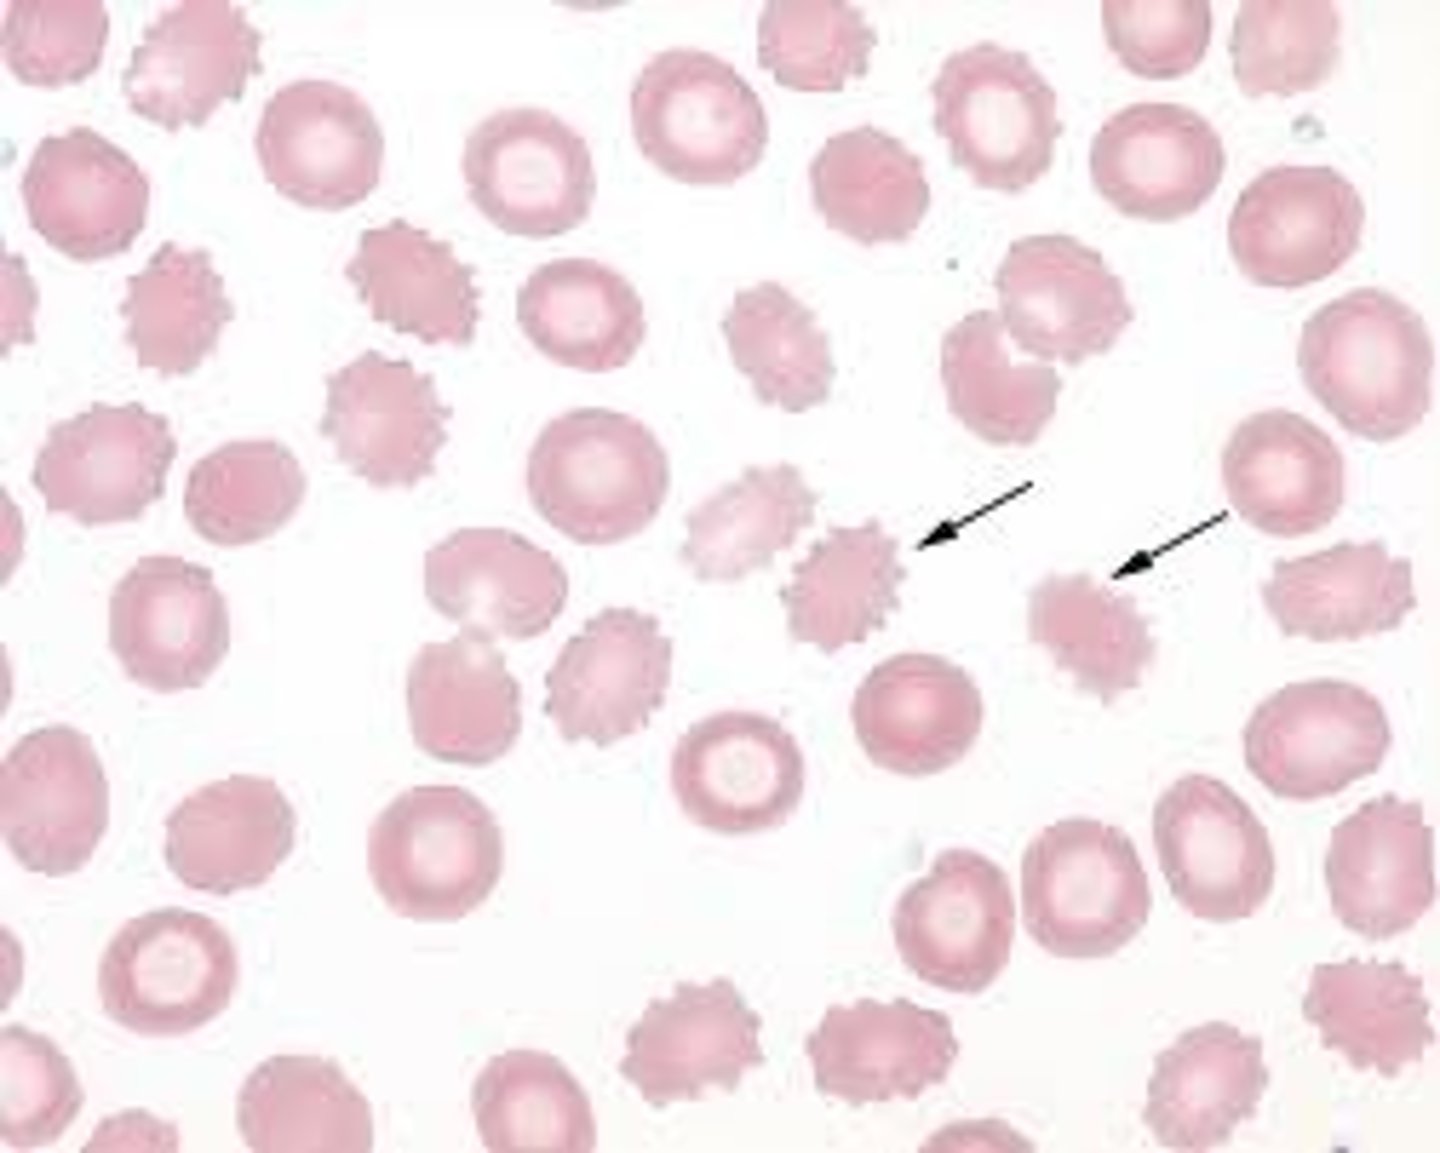

crenation

UNIFORM, evenly spaced, short projections around the RBC's

mainly caused by artifact "old" blood

- too much anticoagulant to blood ratio

burr cells

elliptical shaped

-spiculated with evenly spaced, uniform projections